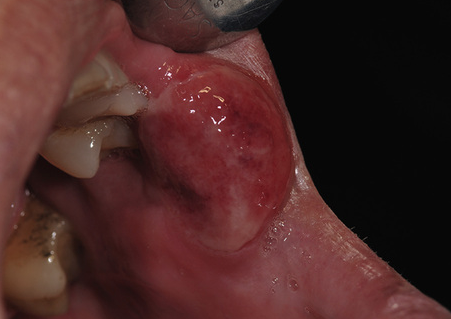

What is the likely diagnosis?

Gumma of tertiary syphilis.